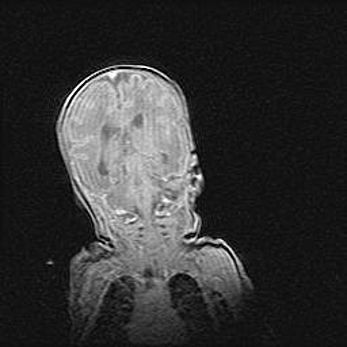

Открытая гидроцефалия.

Возраст: 6 месяцев 15 дней

Вес: 6200 г

Пол: женский

Окружность головы: 41 см

Срок гестации: 38 недель

Гидроцефалия головного мозга у новорожденных – это скопление избыточного количества цереброспинальной жидкости в головном мозге. Ее избыточное скопление в мозге приводит к патологическому расширению желудочков мозга (четырех полостей, расположенных в глубине белого вещества мозга, заполненных цереброспинальной жидкостью и связанных узкими проходами).

Открытый тип гидроцефалии (сообщающаяся) наблюдается тогда, когда нарушен механизм всасывания ликвора в системный кровоток. При этом типе причиной заболевания чаще всего является перенесенные ранее инфекции (например: менингит),  либо же наличие крови в субарахноидальном пространстве.